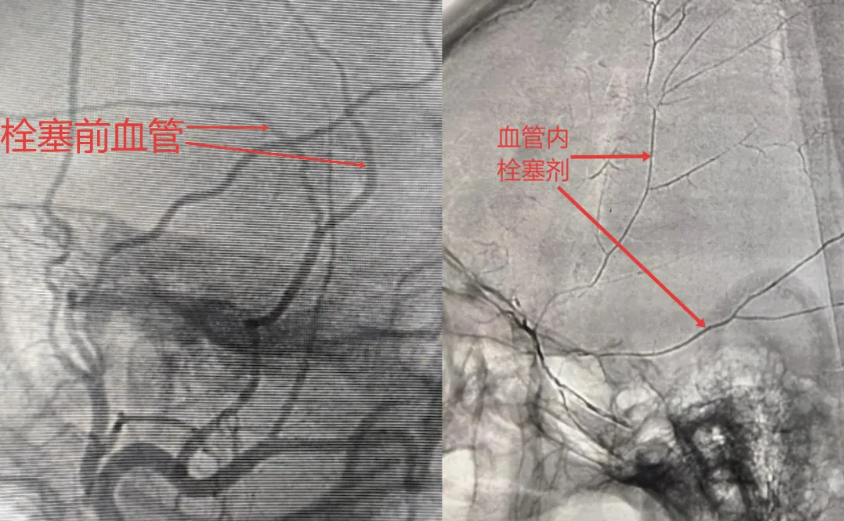

为进一步规范医院VTE防治管理,夯实青年医师基础知识与临床技能,全面提升住院患者静脉血栓栓塞症(VTE)防治能力,有效落实"早发现、早处置"诊疗原则,降低肺栓塞等严重并发症风险。10月23日,西安市红会医院医务部组织开展 VTE 防治管理专题培训。副院长闫亮进行动…